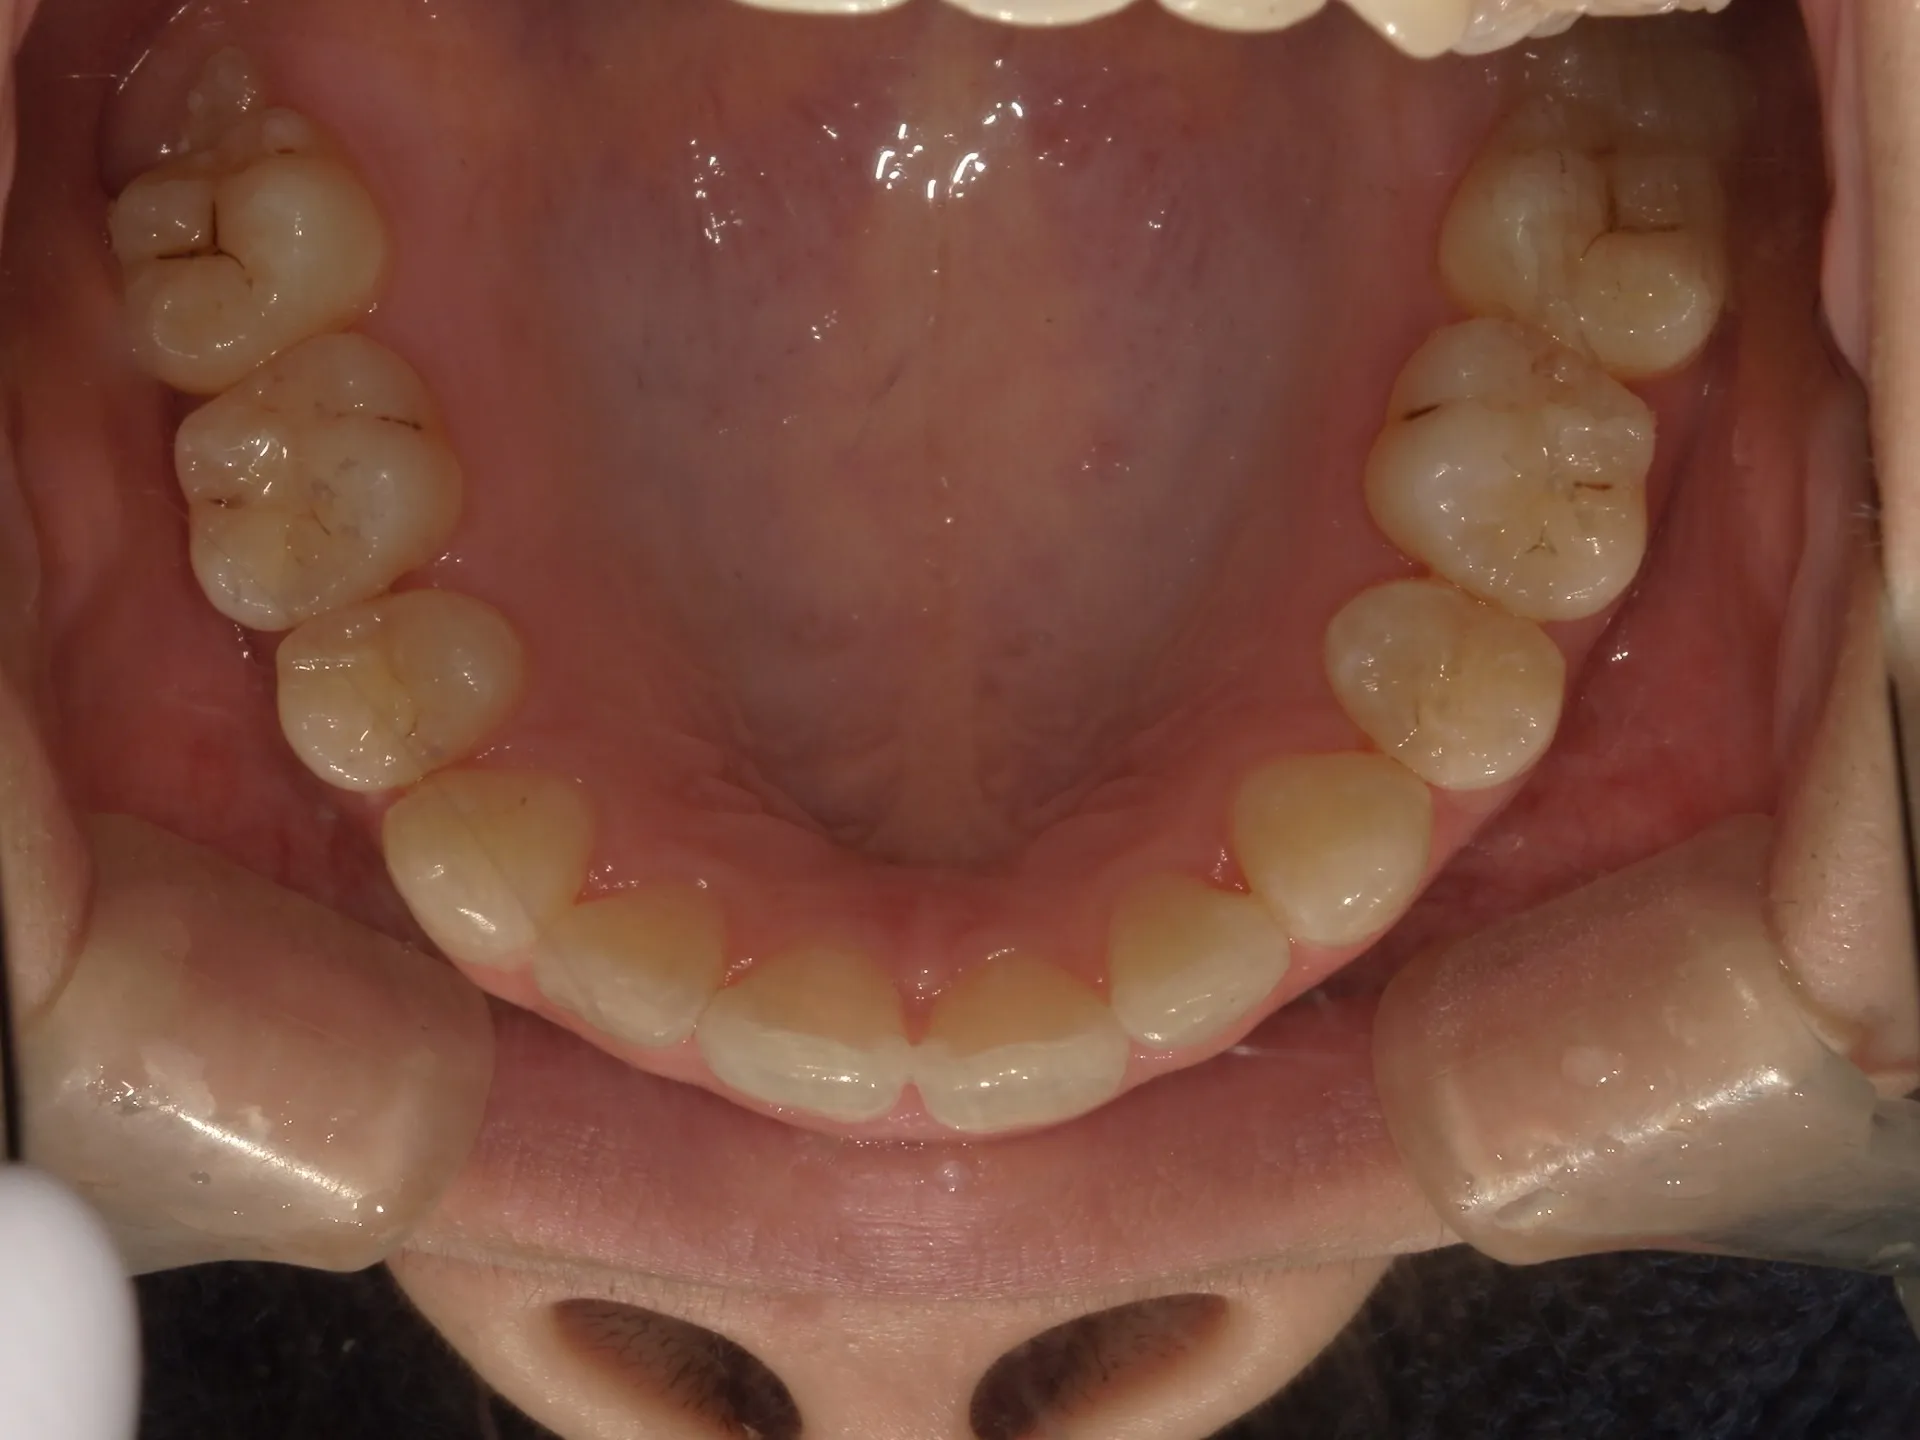

今回はマウスピース矯正(インビザライン)で前歯の出っ張りを治したケースをご紹介いたします。

マウスピース矯正で前歯の出っ歯感を抑えることが可能で、このケースでは上の歯のみ2本の抜歯を行っています。